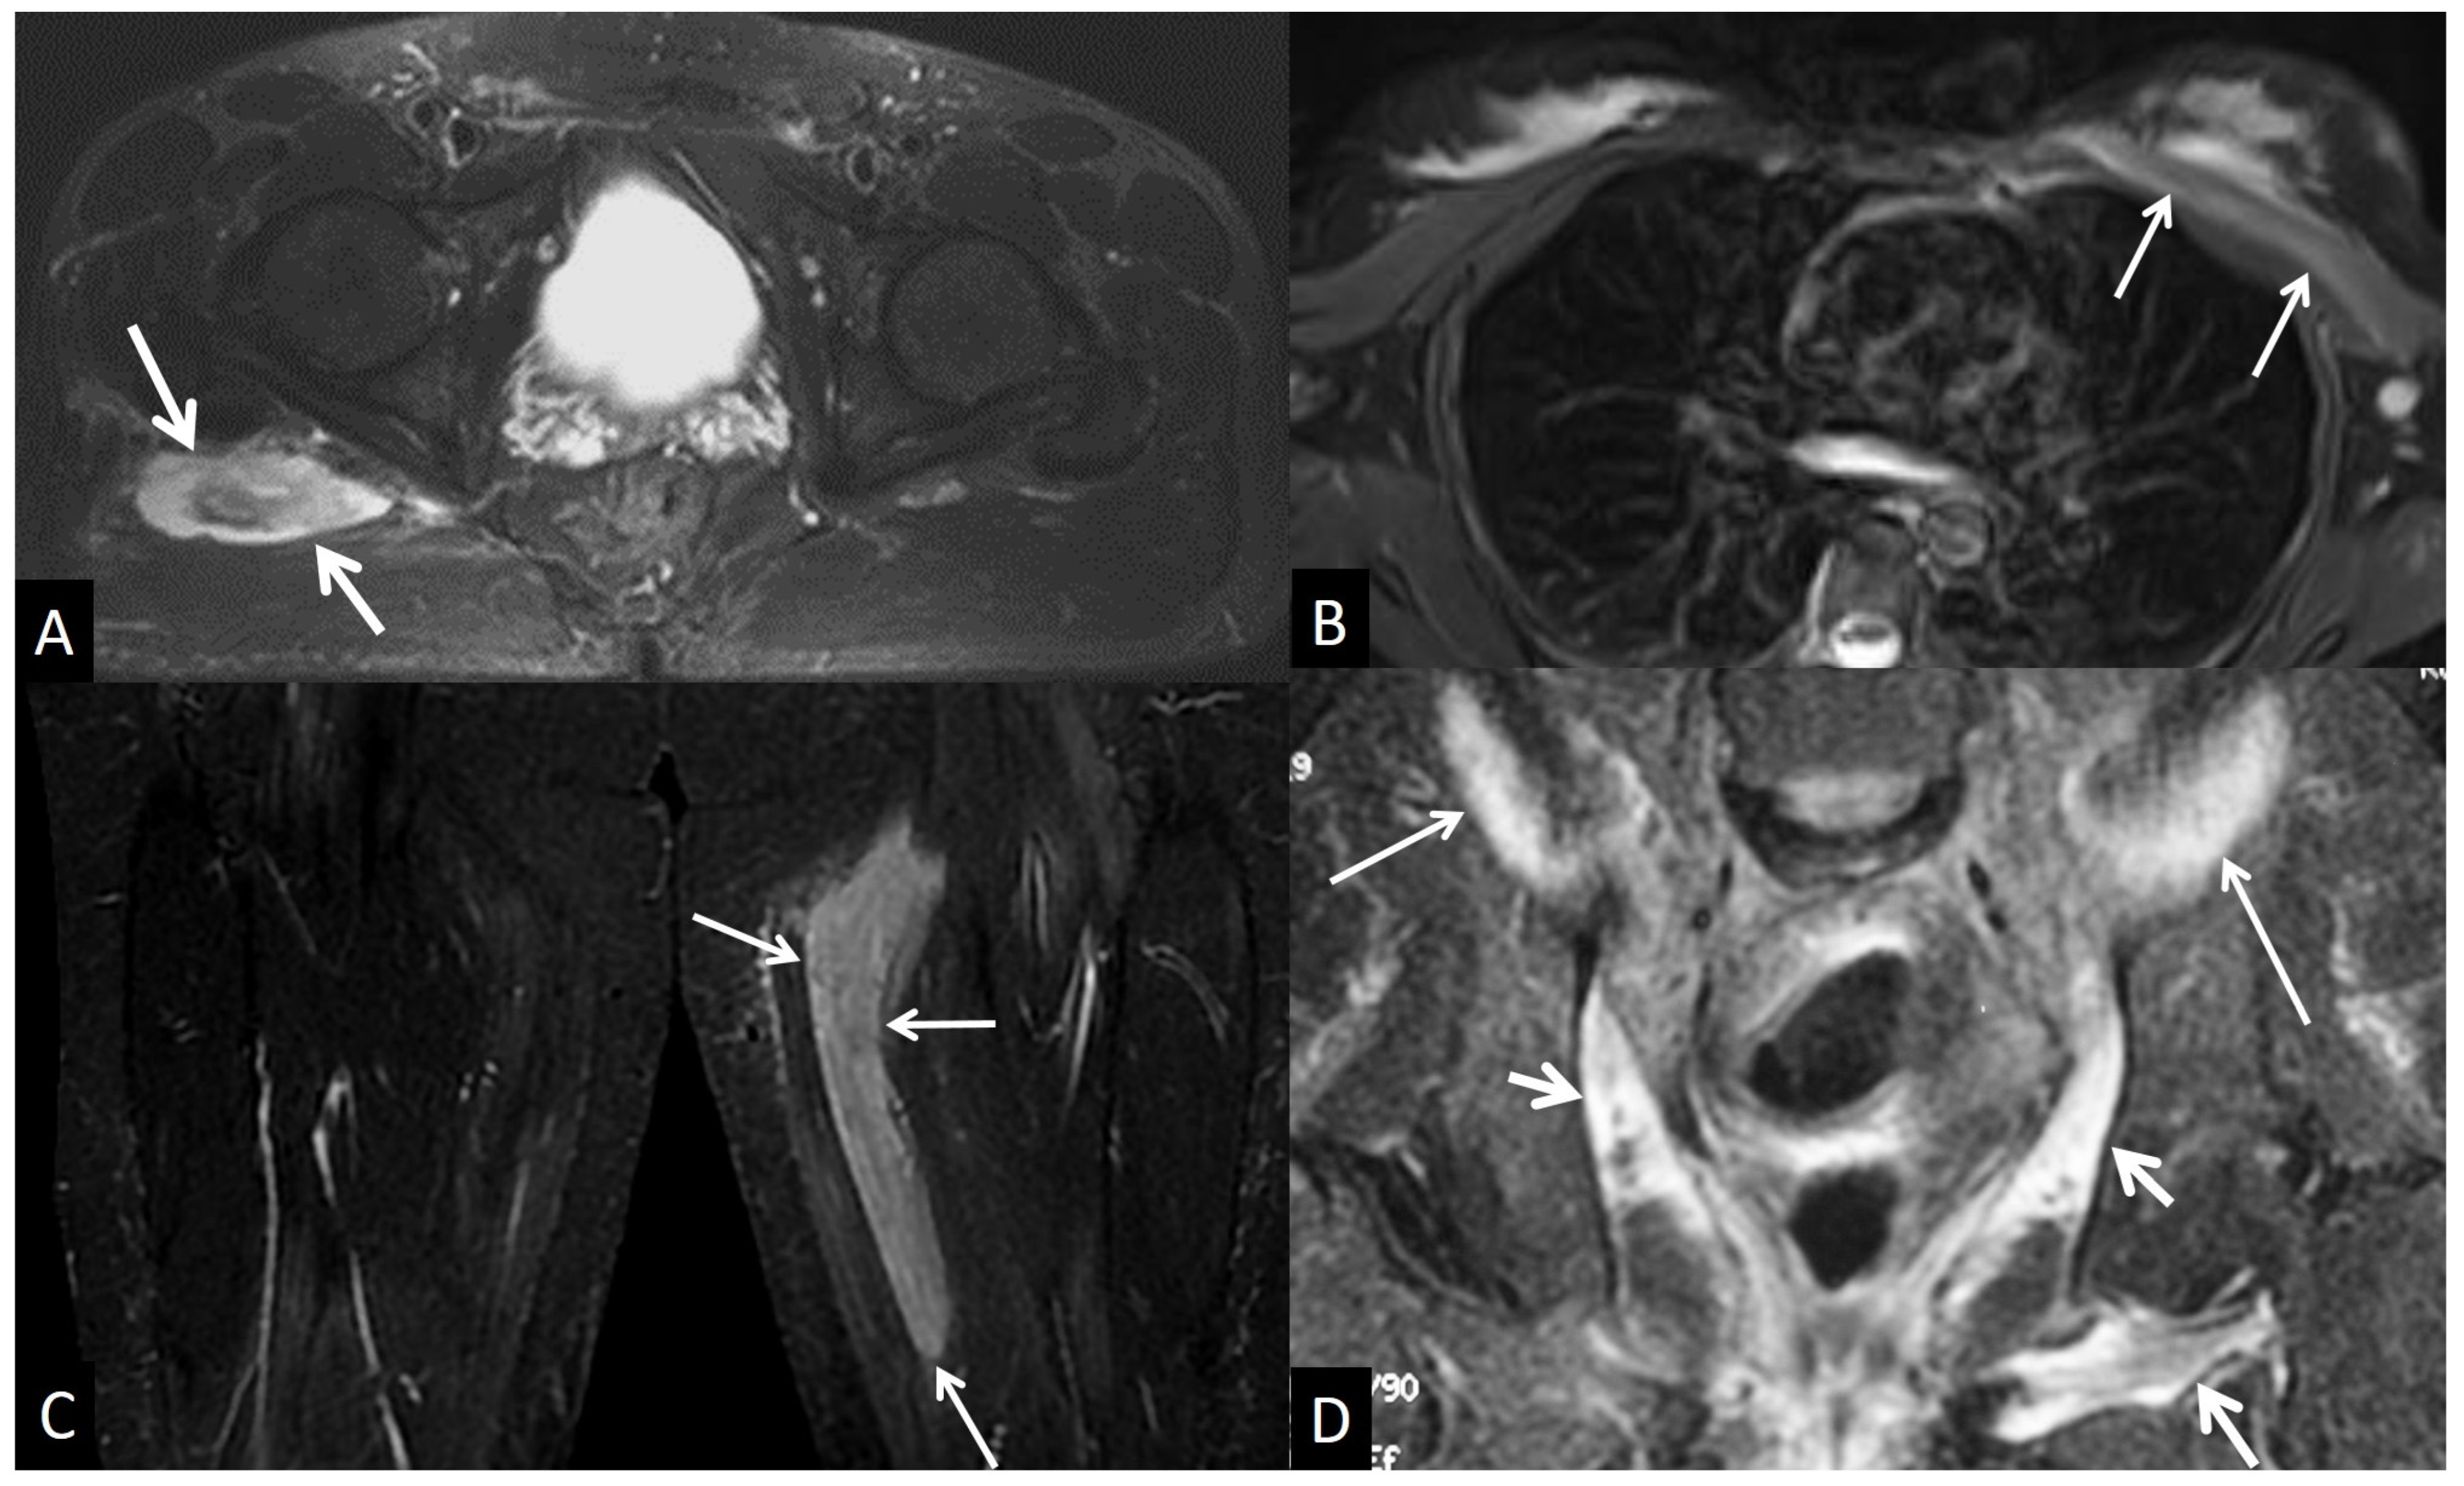

5.2.4. Inflammatory Myopathies

5.4.4. Rhabdomyolysis

5.4.5. Myositis Ossificans

5.5. Neoplasm and Post-Therapy Soft-Tissue Changes

5.5.1. Neoplasms